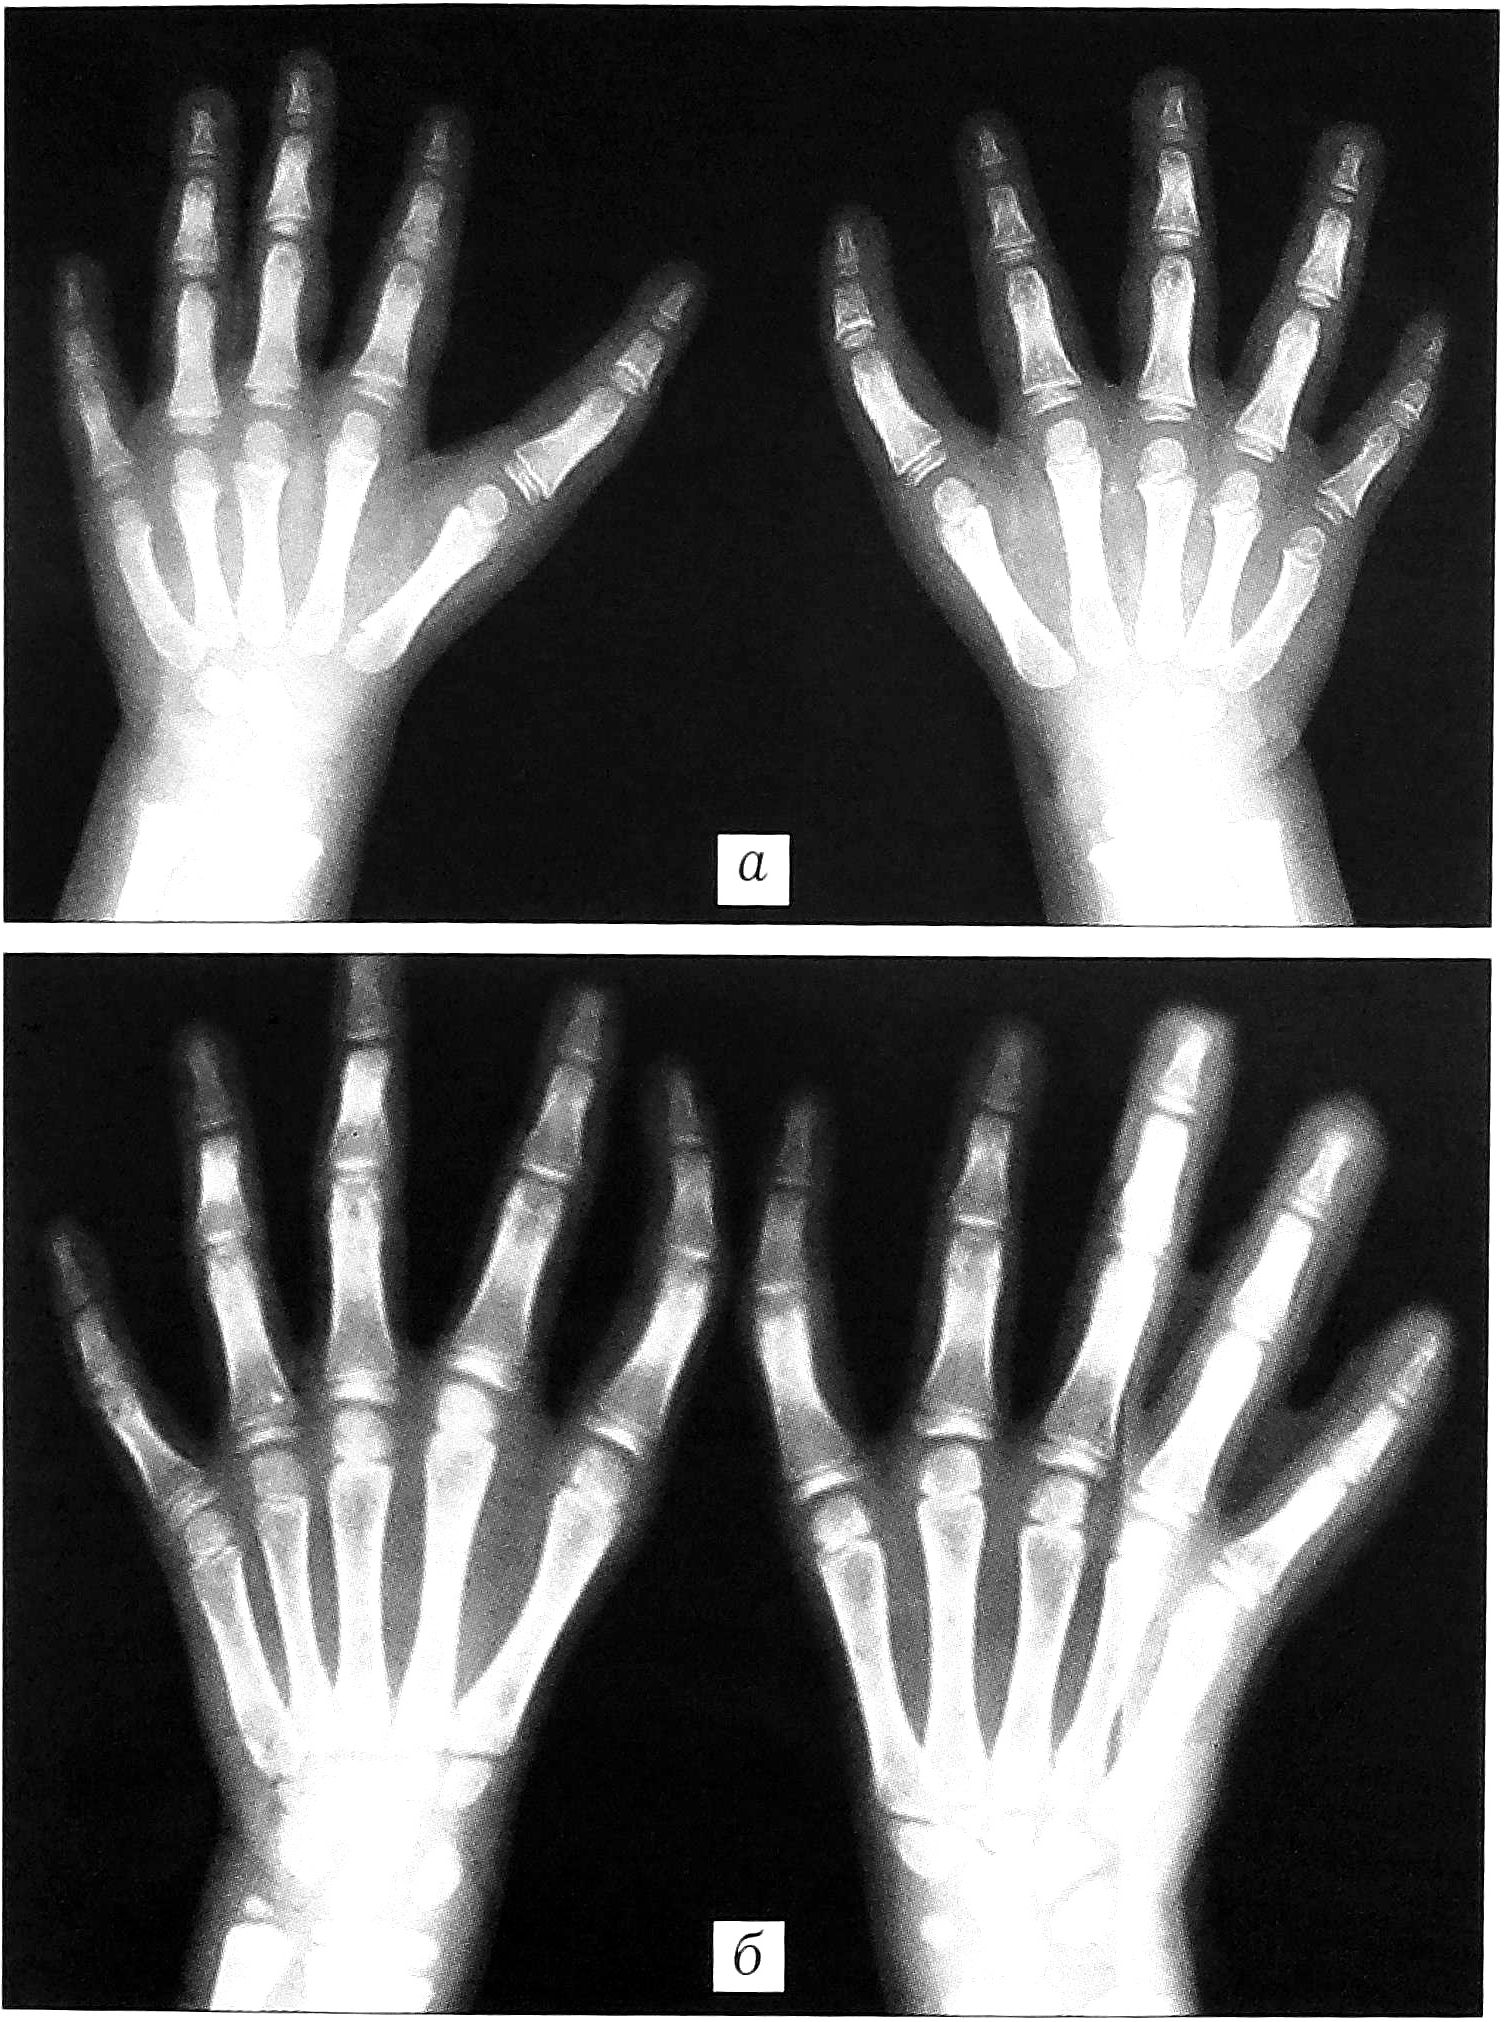

Рис. 4. Долихофалангеальная форма трехфалангизма: а — с нормальным первым межпальцевым промежутком и увеличением I луча до 20% от возрастной нормы; б — с уменьшенным первым межпальцевым промежутком и увеличением I луча на 20-40% от возрастной нормы.

Продольные размеры основной фаланги, как правило, увеличены до 30%, дистальной — уменьшены до 30% от возрастной нормы. Выявлена корреляция между продольными размерами I луча и величиной первого межпальцевого промежутка: по мере увеличения первого показателя второй уменьшается.

Кроме того, нами выделена переходная форма от долихофалангеальной к брахимезофалангеальной, характеризующаяся, в отличие от перечисленных выше признаков долихофалангеальной формы, отсутствием поперечной гипоплазии I пястной кости, менее выраженным увеличением размеров дополнительной фаланги и I луча кисти в целом (до 20%) и отведением I пальца (рис. 5).

Рис. 5. Переходная форма от долихофалангеальной к брахимезофалангеальной.